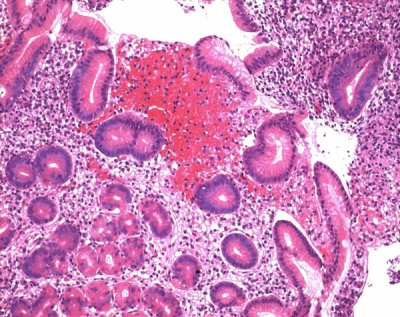

Eosin Y, also called C.I. 45380 or C.I. Acid Red 87, is the form of eosin most commonly used in histology, most notably in the H&E stain. Eosin Y is also widely used in the Papanicolaou stain and the Romanowsky type cytologic stains. It is also used as a photosensitizer in organic synthesis. Wikipedia

ائوزین وای اصولا به عنوان لکه استفاده می شود که از آن برای تعیین محل بخش های مغزی ، برای رنگ آمیزی بافت کبد ثابت و برای معاینه بافت شناسی بخش های مغزی از هیپوکامپ پشتی استفاده می شود.

همچنین ائوزین وای برای رنگ کردن سیتوپلاسم، کلاژن و فیبرهای ماهیچه ای جهت معاینه در زیر میکروسکوپ مورد استفاده قرار می گیرد.

Eosin Y همچنین به طور گسترده در رنگ آمیزی پاپانیکولائو و لکه های سیتولوژیک نوع Romanowsky استفاده می شود. همچنین به عنوان یک حساس کننده نور در سنتز آلی استفاده می شود.